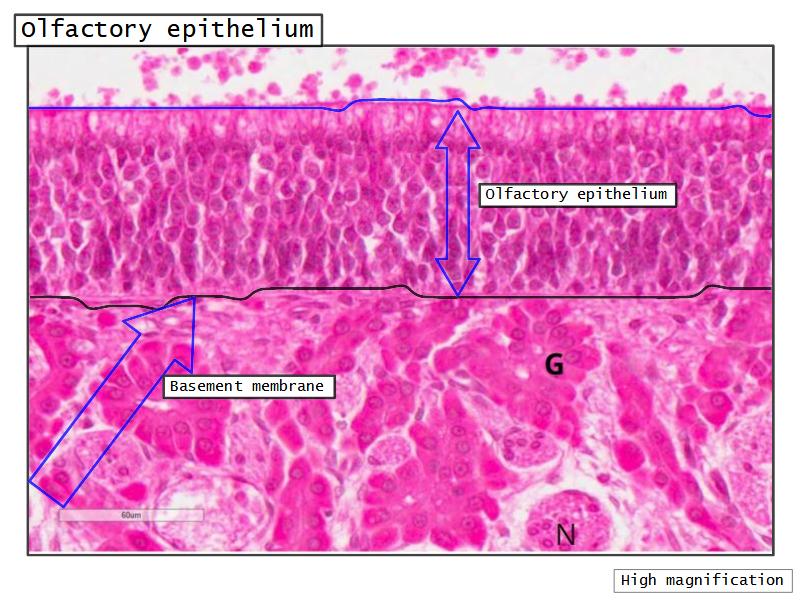

- Slide 108: Olfactory epithelium

Olfactory epithelium